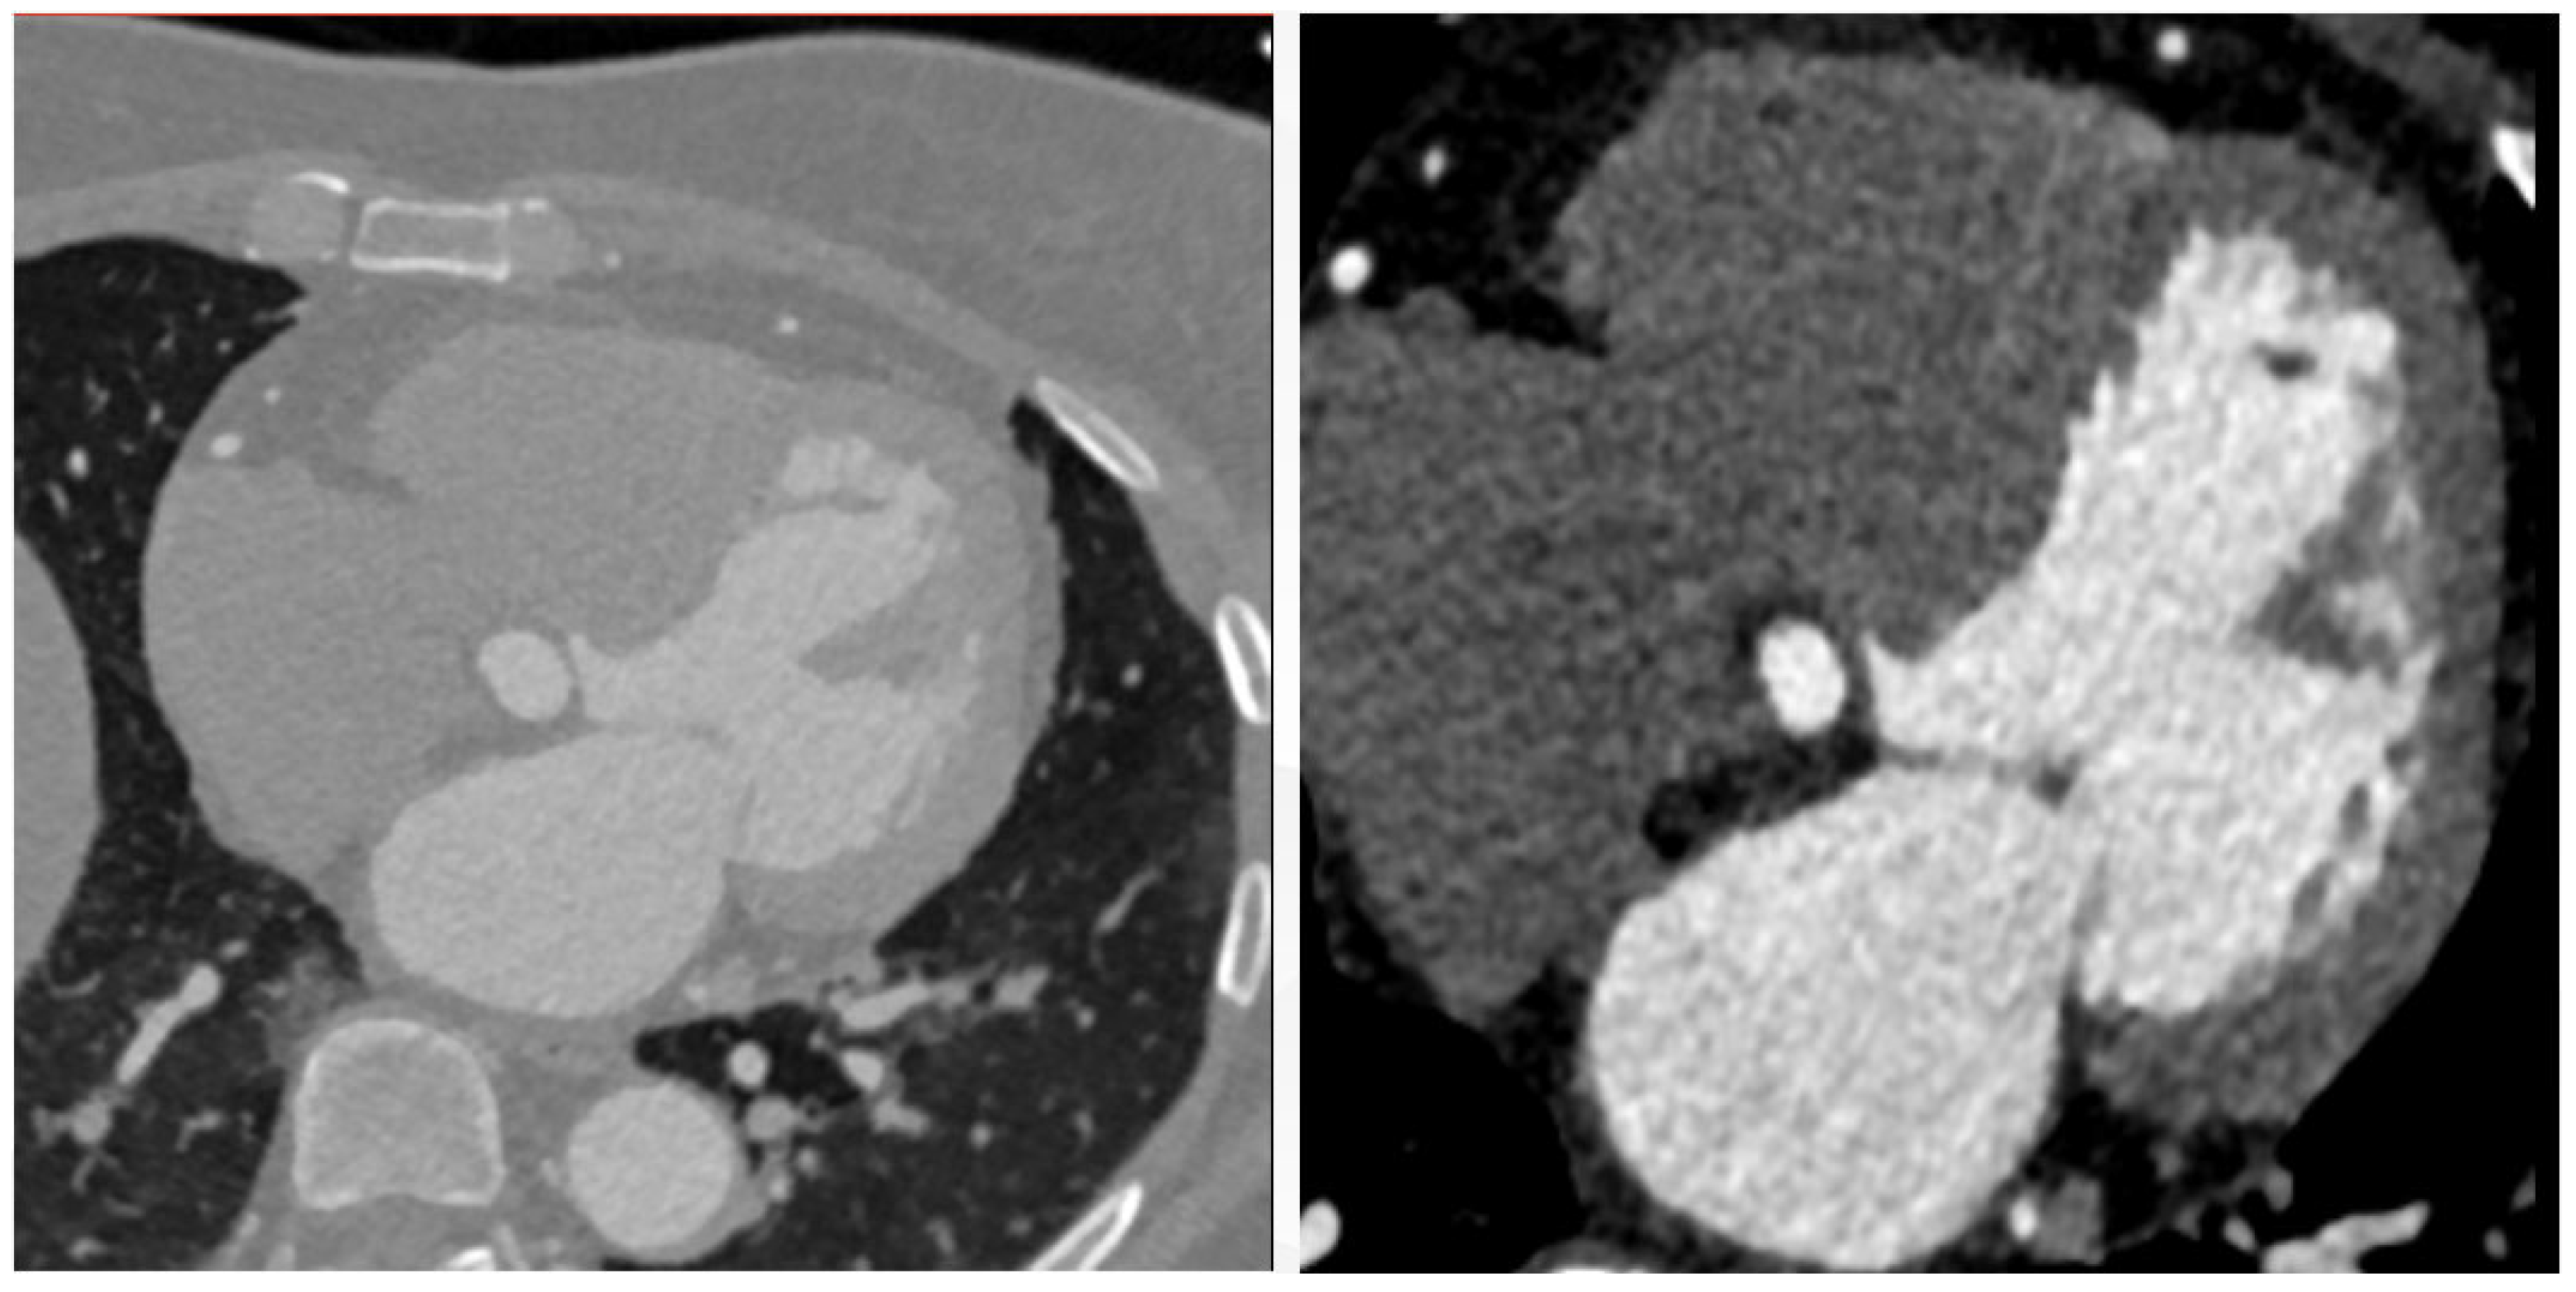

4.1. Datasets and Preprocessing

4.4.2. Qualitative Results